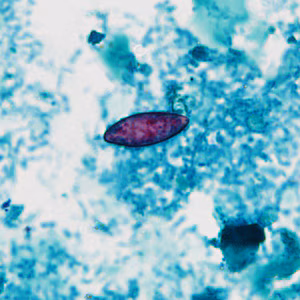

Case #430 – October, 2016

A 25-year-old refugee from Myanmar had a stool specimen collected for routine ova-and-parasite examination as part of a post-arrival screening. Figures A–D show what was found in moderate numbers on a fecal smear stained with Kinyoun’s modified acid-fast stain. The objects measured 20 micrometers on average. What is your diagnosis? Based on what criteria?